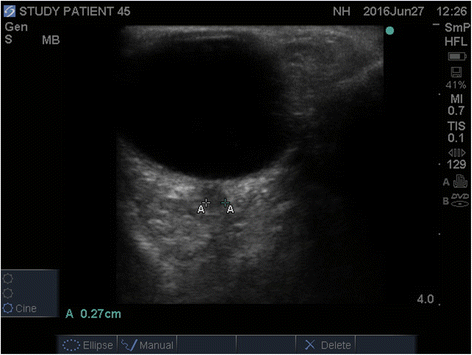

Background: Unexplained coma after critical illness can be multifactorial. We evaluated the diagnostic ability of bedside Optic Nerve Sheath Diameter [ONSD] as a screening test for non-traumatic radiographic cerebral edema.

Methods: In a prospective study, mixed medical-surgical intensive care units [ICU] patients with non-traumatic coma [GCS < 9] underwent bedside ultrasonographic ONSD measurements. Non-traumatic radiographic cerebral edema [NTRCE] was defined as > 5 mm midline shift, cisternal, sulcal effacement, or hydrocephalus on CT.

Results: NTRCE was identified in 31 of 102 patients [30.4 %]. The area under the ROC curve for detecting radiographic edema by ONSD was 0.785 [95 % CI 0.695-0.874, p <0.001]. ONSD diameter of 0.57 cm was found to be the best cutoff threshold with a sensitivity 84 % and specificity 71 %, AUC 0.785 [95 % CI 0.695-0.874, p <0.001]. Using ONSD as a bedside test increased the post-test odds ratio [OR] for NTRCE by 2.89 times [positive likelihood ratio], whereas post-test OR for NTRCE decreased markedly given a negative ONSD test [ONSD measurement less than 0.57 cm]; negative likelihood ratio 0.22.